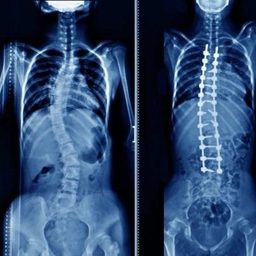

Что такое сколиоз, как его диагностируют и лечат

Всё о заболевании, его признаках и вариантах терапии.